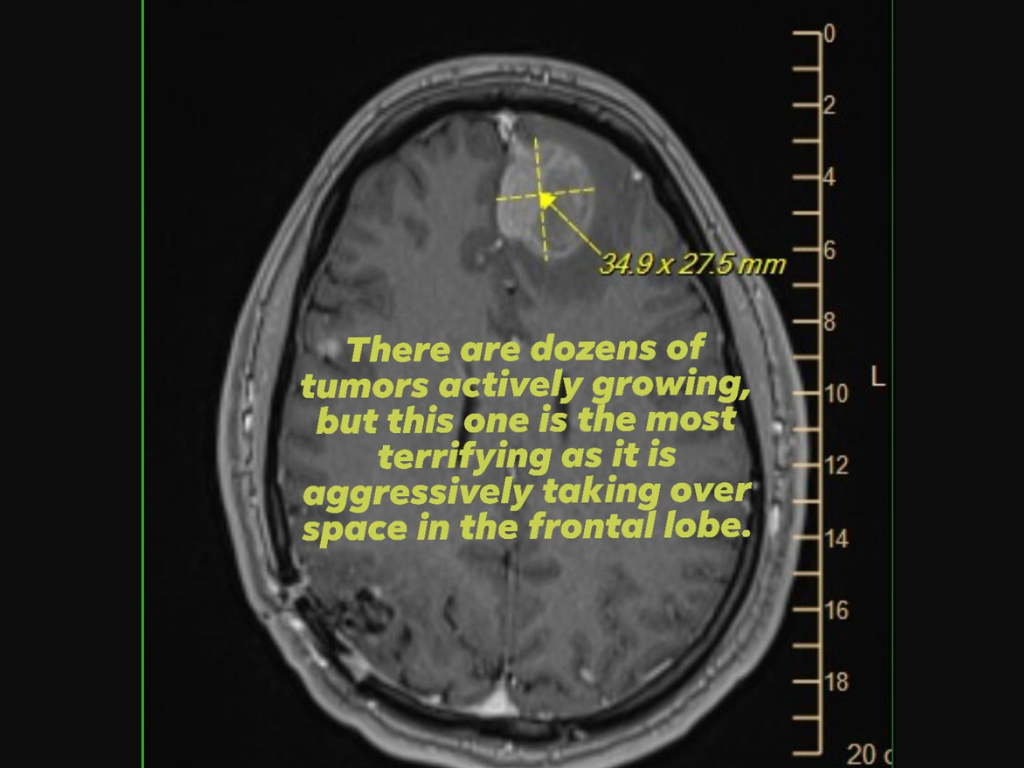

В качестве доказательства она также приложила снимок сканирования мозга (МРТ), который показал агрессивную опухоль лобной доли, и обратилась за поддержкой или помощью к руководителям Epic Games, которые принимали ключевые решения об увольнениях.